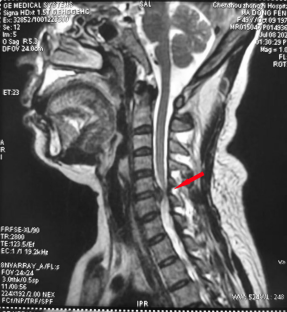

一、脊柱疾病

頸椎病治療前 頸椎病治療后 腰椎間盤突出癥治療前、后